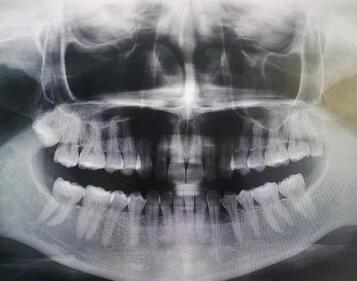

一直对自己的牙齿不太满意,想做牙齿矫正,经过多方打听和朋友的推荐,后我鼓起勇气来到了佛山穗华口腔,穗华口腔的位置容易找到,工作人员也积极主动,热心,进门需要测温,扫码。一进门先检查口腔情况,医生先带我做了一个口扫,摸清牙齿的情况。接着做 CT ,等结果出来之后到诊室和医生进行一对一的沟通,制定治疗方案。期待自己的变化。